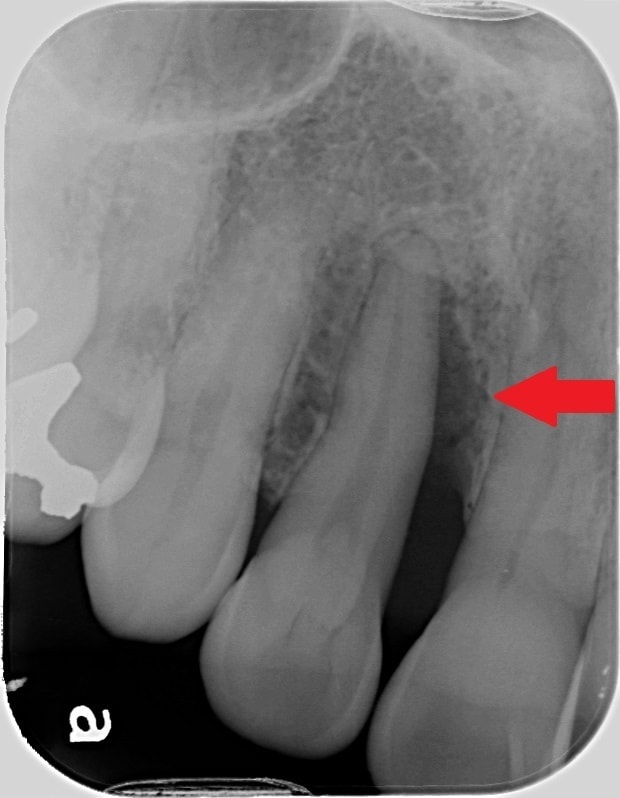

初診時のレントゲンで、赤の矢印が示す黒いところは、簡単に言うと歯周病で歯の周りの骨が溶けてしまっている状態です。

歯周組織再生療法という歯の周りの骨の再生を促す手術後2年6ヶ月後のレントゲンでは、緑の矢印で示すように、黒かったところが白く変わっていることが分かるかと思います。溶けてしまっていた骨の再生が、促されていることが推測されます。

このような治療効果も、患者さんご自身でのブラッシングの状態が悪いと長持ちしません。